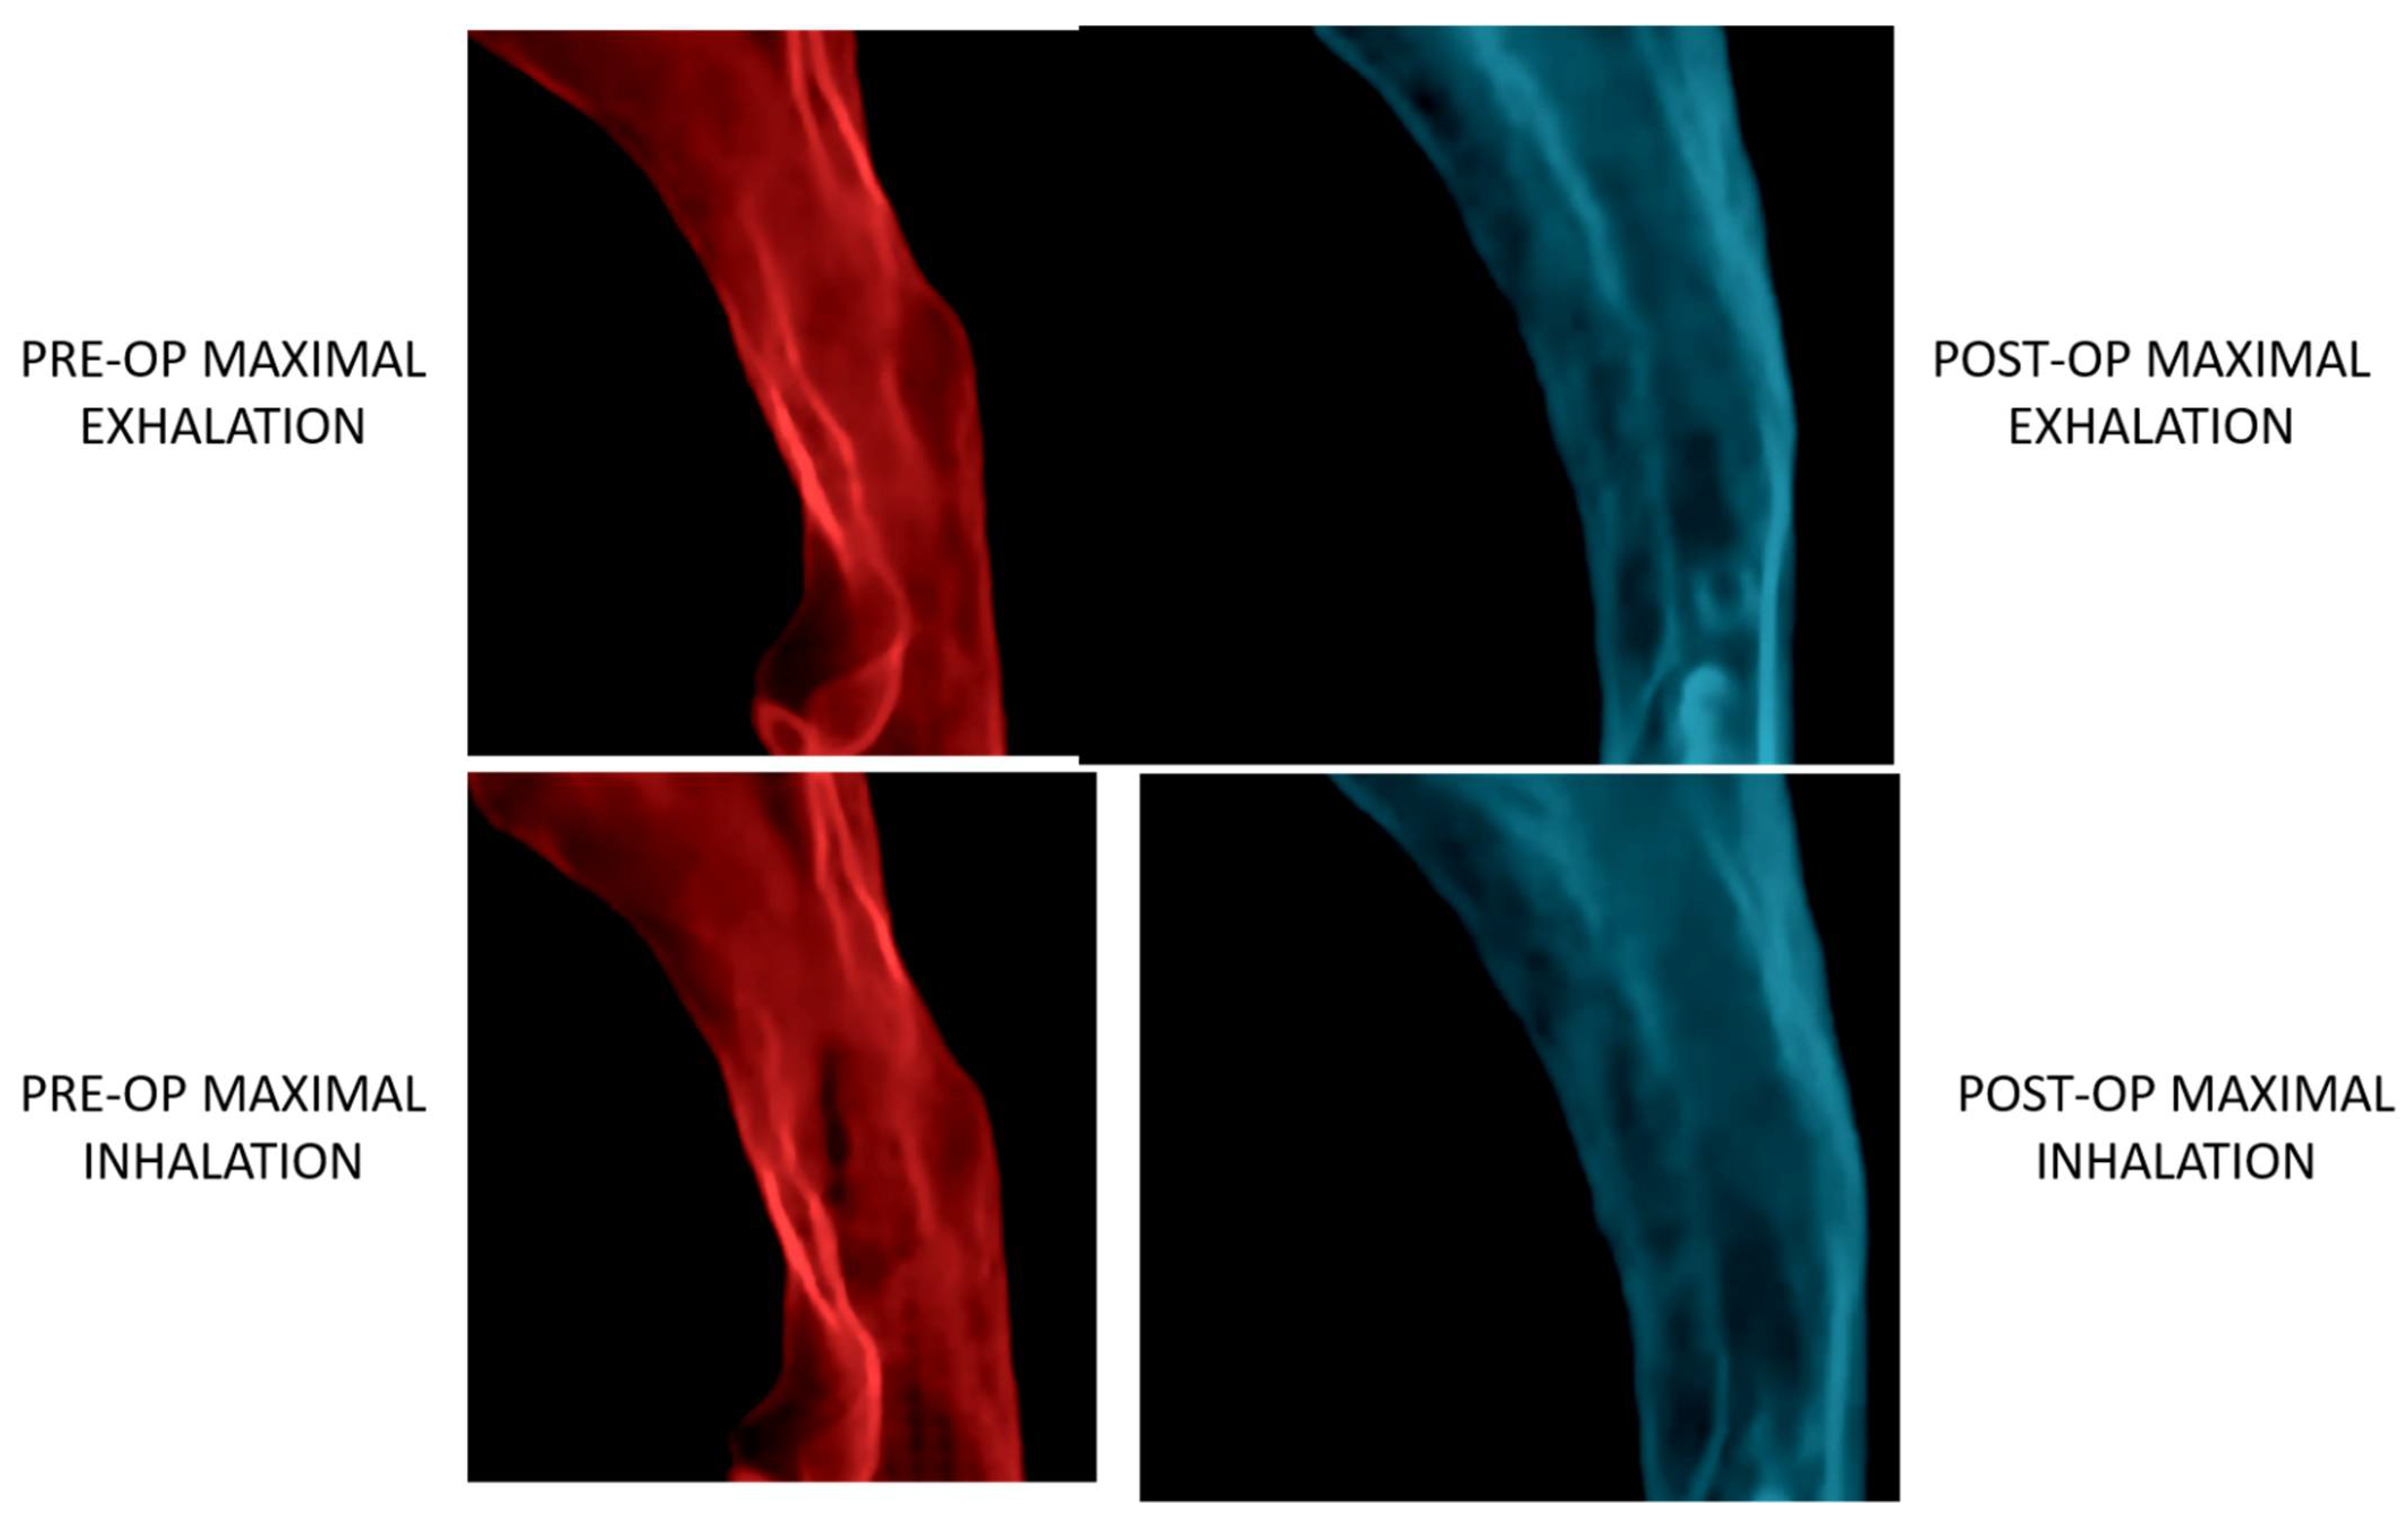

4. Orthognathic Surgery for Obstructive Sleep Apnea

4.4. Orthognathic Surgery for the Treatment of OSA

- Steegman, R.; Hogeveen, F.; Schoeman, A.; Ren, Y. Cone beam computed tomography volumetric airway changes after orthognathic surgery: A systematic review. Int. J. Oral Maxillofac. Surg. 2023, 52, 60–71. [Google Scholar] [CrossRef]

- Fleck, R.J.; Ishman, S.L.; Shott, S.R.; Gutmark, E.J.; McConnell, K.B.; Mahmoud, M.; Mylavarapu, G.; Subramaniam, D.R.; Szczesniak, R.; Amin, R.S. Dynamic Volume Computed Tomography Imaging of the Upper Airway in Obstructive Sleep Apnea. J. Clin. Sleep Med. 2017, 13, 189–196. [Google Scholar] [CrossRef]

- Abramson, Z.; Susarla, S.M.; Lawler, M.; Bouchard, C.; Troulis, M.; Kaban, L.B. Three-dimensional computed tomographic airway analysis of patients with obstructive sleep apnea treated by maxillomandibular advancement. J. Oral Maxillofac. Surg. 2011, 69, 677–686. [Google Scholar] [CrossRef]